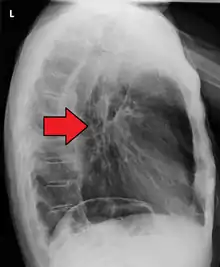

Esophageal cancer (lower part) as a result of Barrettʼs esophagus

Male predominance is particularly strong in this type of esophageal cancer, which occurs about 7 to 10 times more frequently in men.[25] This imbalance may be related to the characteristics and interactions of other known risk factors, including acid reflux and obesity.[25]

The long-term erosive effects of acid reflux (an extremely common condition, also known as gastroesophageal reflux disease or GERD) have been strongly linked to this type of cancer.[26] Longstanding GERD can induce a change of cell type in the lower portion of the esophagus in response to erosion of its squamous lining.[26] This phenomenon, known as Barrett's esophagus, seems to appear about 20 years later in women than in men, possibly due to hormonal factors.[26] At a mechanistic level, in the esophagus there is a small HOXA13 expressing compartment that is more resistant to bile and acids as the normal squamous epithelium and that is prone to both intestinal differentiation as well as oncogenic transformation. Following GERD this HOXA13-expressing compartment outcompetes the normal squamous compartment, leading to the intestinal aspect of the esophagus and increased propensity to the development of esophageal cancer.[27] Having symptomatic GERD or bile reflux makes Barrett's esophagus more likely, which in turn raises the risk of further changes that can ultimately lead to adenocarcinoma.[16] Bile reflux containing unconjugated bile acids, including deoxycholic acid and chenodeoxycholic acid, appears to contribute to esophageal adenocarcinoma carcinogenesis by inducing oxidative stress and DNA damage[28].The risk of developing adenocarcinoma in the presence of Barrett's esophagus is unclear, and may in the past have been overestimated.[2]